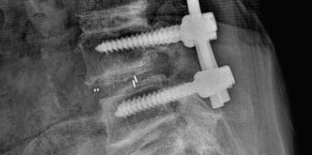

사실 나이가 들어서 생기는 퇴행성 질환인 척추관 협착증을 자가진단 및 예방으로 완치하는 것은 불가능합니다. 오랜 시간 동안 압박으로 인해 두꺼워진 인대와 좁아진 척추관의 자연치유는 불가능하다고 할 수 있습니다. 그리고 심한 경우에는 수술적 치료가 반드시 필요합니다. 다만, 증세가 심하지 않을 경우에는 비수술적 치료인 약물 복용과 주사 투여 시술 등을 통해 신경이 눌린 척추관 혈액순환을 증진시켜 일시적으로 통증을 완화할 수 있습니다. 그러나 이 같은 비수술적 치료는 시간이 지나면서 다시 재발할 수밖에 없습니다. 따라서 척추관 협착증을 근본적으로 치료하는 방법은 자가진단 및 예방과 더불어 수술입니다. 수술을 할 경우에는 수술을 하기 전보다 50% 이상의 환자가 증상 호전을 경험했으며, 수술방법은 크게 ① 척수와 신경 사이 공간을 넓히는 '추궁 절제술'과 ② 척추 뼈를 결합해 척추 안정성을 강화하는 '척추 융합 수술' 두 가지로 구분됩니다. ③ 허리 부위 쪽에 척추관 협착증 증상이 심할 경우에는 두 가지 수술 방법을 결합하기도 합니다. 그렇다면 척추관 협착증 수술비용은 얼마나 들까요? 증상 정도와 진행율에 따라 다소 차이는 있지만 수술비용은 대략 1천만 원까지 1천5백만 원까지 생각하셔야 합니다. 의료보험이 적용되지만 MRI 검사와 각종 주사제 등이 비급여 항목이기 때문에 수술비용이 비싼 편입니다. 참고로 수술시간은 2시간 내외입니다. 이처럼 일상생활에 불편을 주고 비용적 부담이 크기 때문에 척추관 협착증 자가진단 및 예방이 중요합니다. 그렇다면 예방책은 무엇일까요?